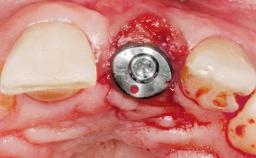

Late Placement of an Implant in a Maxillary Left Central Incisor Site

Type of Implants Two-Piece

Attachment Two-Piece

Bone Augmentation Horizontal|Staged

Augmentation Materials Xenogenous|Membrane